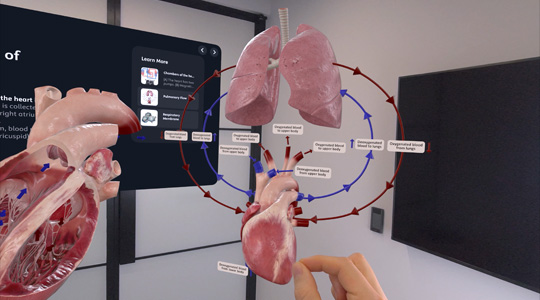

Work with everyday business apps in an unlimited, interactive space. Streamline collaboration with Microsoft 365 Copilot, Zoom, and Webex. Accelerate data analysis and visualization at scale with platforms like SAP, Salesforce, and NVIDIA Omniverse. And bring projects and training programs to life with incredible visionOS apps that are ready for enterprise.